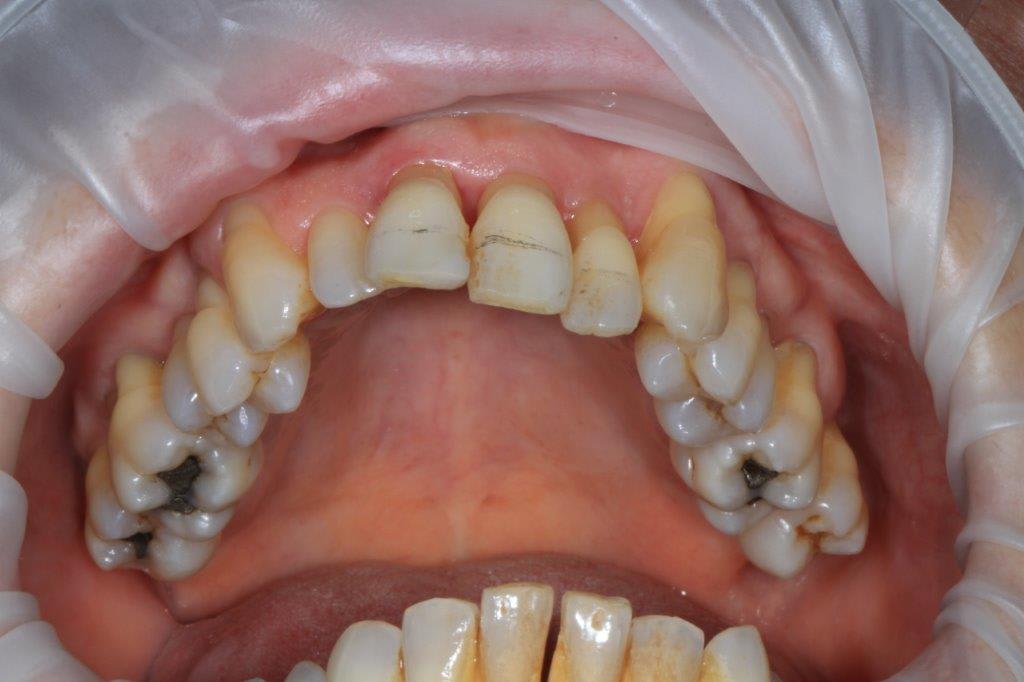

un peu de grain à moudre, toutes les critiques sont les bienvenues...

1ere séance,"nettoyage...", et après réflexion, plutôt que le nettoyage par le vide, attelle de contention pour le bloc antérieur mandibulaire, suppression de quelques contact très parasite sur les pm et canines, et réduction des incisives mandibulaire puis maxillaire... consignes de brossages / bain de bouche avec .... l'érythritol afin de ne pas mourir idiot... on verra ce que ça donne dans un cas relativement perdu d'avance.... merci Algi... enfin peut être : -))

C est dommage que l'on ne voit pas les dents en occlusion .

La 12 est en occlusion inverse et le secteur postérieur 20/30 aussi ?